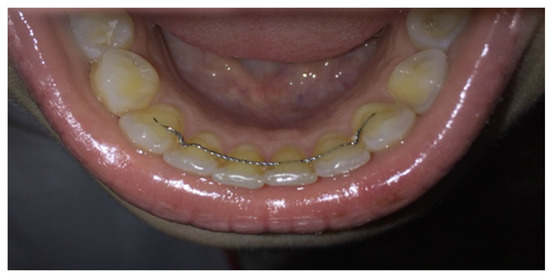

However, in an attempt to achieve a more aesthetic retention method in 1971 a transparent retainer was designed [20] (Figure 2). Vacuum-formed retainers (VFRs) are easier to make and cheaper than the Hawley retainers (HRs). The VFRs are easy to replace if they deteriorate or fracture. Patients’ compliance is much better when wearing VFRs because they do not interfere with the palate and cause vomiting reflex. Their occlusal thickness prevents vertical movements that are possible in the case of HRs [16,17,18,19,20].

Figure 2. Inferior vacuum-formed retainer used in the study.